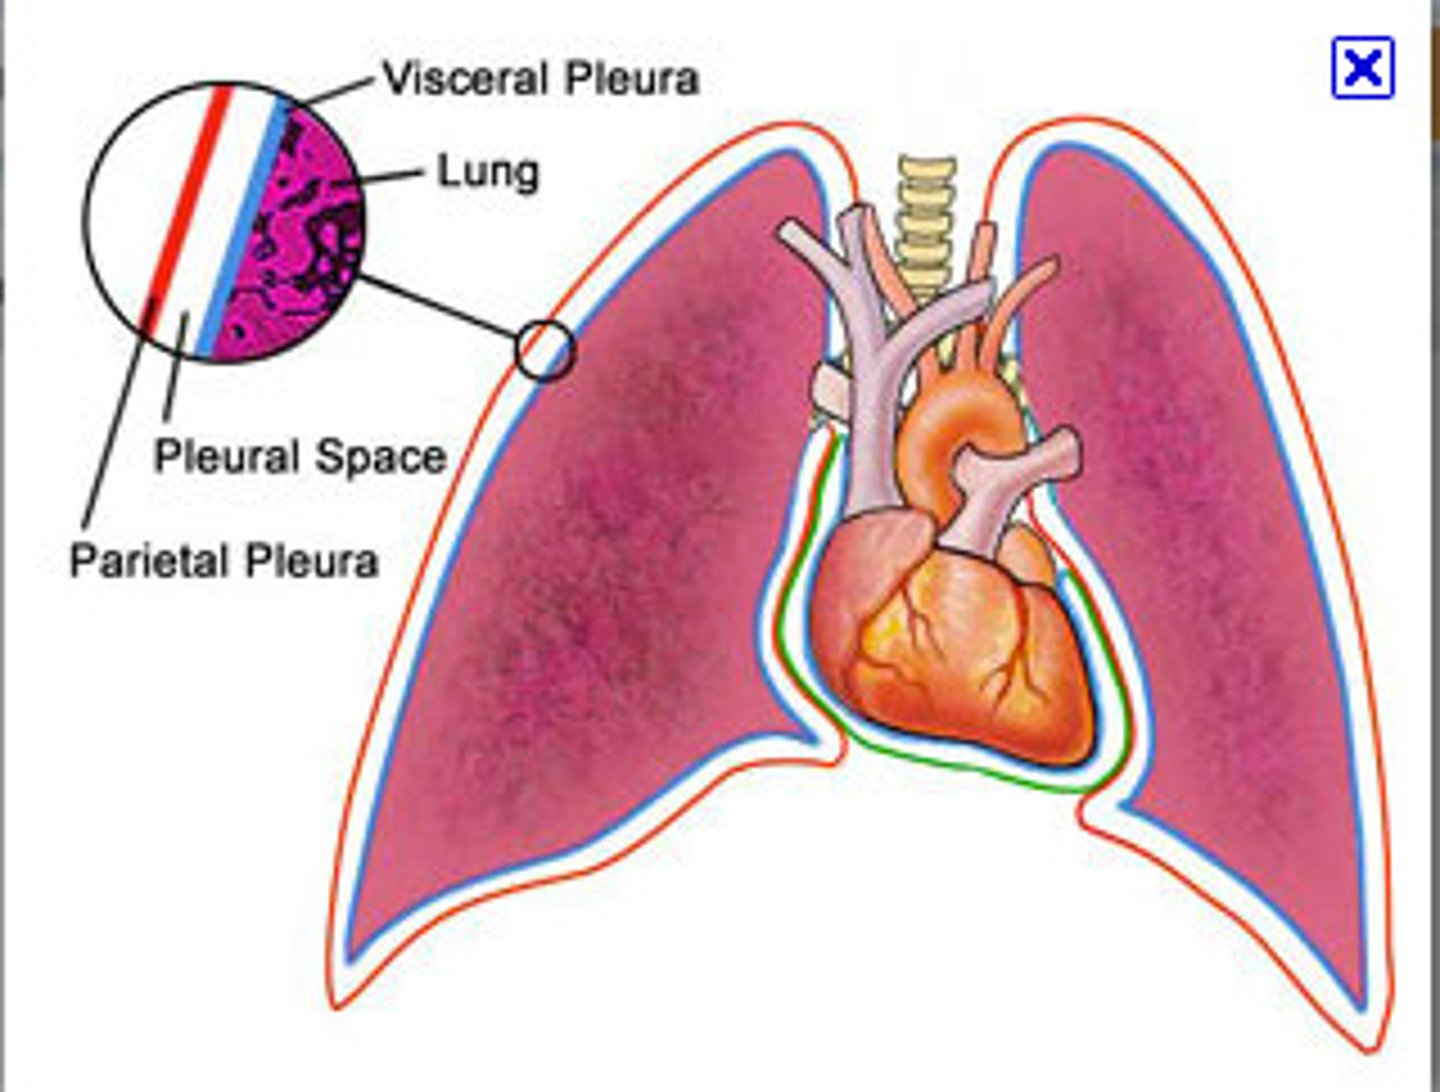

pleurae

thin, double-layered serosal membrane that divides thoracic cavity into two pleural compartments and mediastinum

parietal pleura

outermost layer of the pleura that connects to the thoracic wall, mediastinum, and diaphragm

visceral pleura

innermost layer of the pleura that is superficial to the lungs and extends into the lung fissures

pleural cavity

space between the visceral and parietal pleurae

pleural fluid

substance that acts as a lubricant for the visceral and parietal layers of the pleura during the movement of breathing